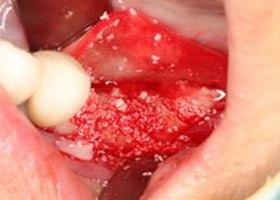

5. 重新進行骨頭再生手術。

![proimages/case/Artificial_implant/save-defeat03-2.jpg proimages/case/Artificial_implant/save-defeat03-2.jpg]()